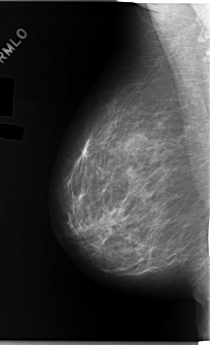

C_0170_1.RIGHT_MLO

RIGHT_MLO LINES 5856 PIXELS_PER_LINE 3560 BITS_PER_PIXEL 12 RESOLUTION 50 NON_OVERLAY